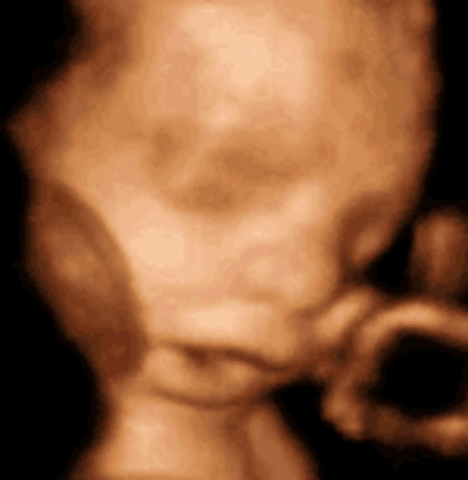

• Week 20 of the Second Trimester

Week 20 of the Second Trimester

This is the mid point in the pregnancy, the Fetus can now process outside noises and will become familliar with common voices.

Facts:

1)Baby now weighes about 11 ounces and is roughly 7 inches long.

2)The mother will probably start feeling the first fetal movements.